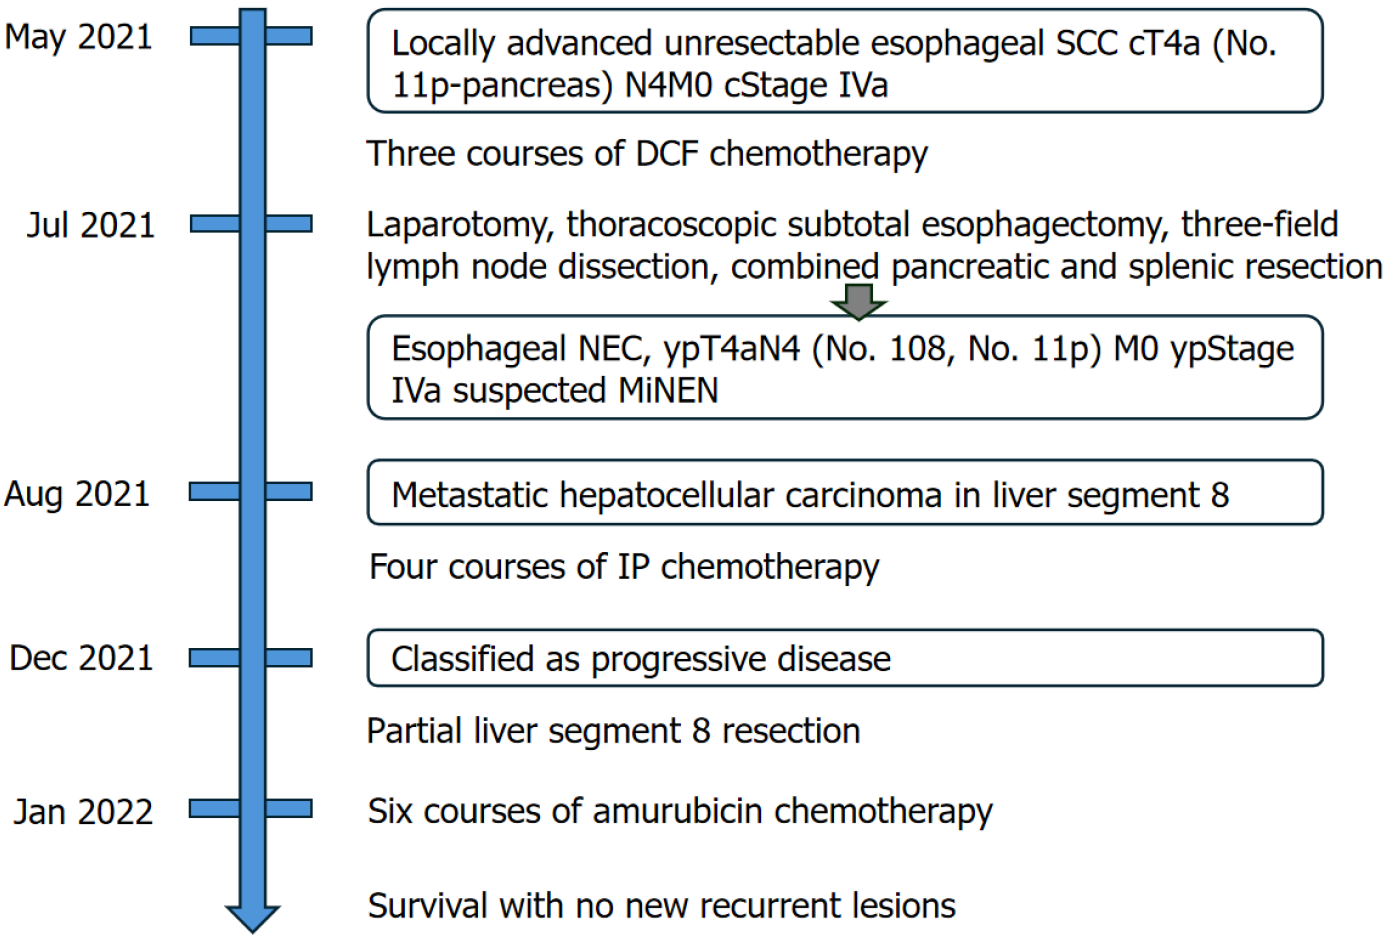

Esophageal neuroendocrine carcinoma (NEC), a rare and aggressive malignancy with a poor prognosis, is often diagnosed at an advanced stage. The optimal treatment strategy for locally advanced and recurrent esophageal NEC remains unclear, and conversion surgery has only been reported for a few cases. Herein, we present the case of a 66-year-old male with locally advanced esophageal NEC initially diagnosed as squamous cell carcinoma.

The patient underwent induction chemotherapy with docetaxel, cisplatin, and 5-fluorouracil, followed by conversion surgery, including subtotal esophagectomy, three-field lymph node dissection, and distal pancreatectomy with splenectomy, due to infiltration of the pancreas by the No. 11p lymph node. Postoperative pathological findings revealed a large cell-type NEC without a squamous cell carcinoma component, suspected to be a mixed neuroendocrine/non-neuroendocrine neoplasm. Hepatic metastasis was diagnosed within one month of surgery. Despite the administration of four courses of irinotecan + cisplatin chemotherapy, the treatment effect was considered a ‘progressive disease’. After a multidisciplinary discussion, the patient underwent partial liver resection, followed by second-line chemotherapy with amrubicin. The patient achieved three-year survival with no new recurrence.

EGD revealed a semicircular, type 3 tumor in the middle thoracic esophagus, located 29-36 cm from the incisors (Figure 1A). Histopathological analysis of the biopsy specimen confirmed SCC. Computed tomography (CT) revealed irregular wall thickening from the middle to the lower thoracic esophagus, corresponding to the primary lesion (Figure 2A). In addition, an enlarged No. 101L lymph node measuring 15 mm was observed (Figure 2B), along with bulky suprapancreatic lymph node metastasis involving No. 8 and No. 9, forming a mass; furthermore, No. 11p was enlarged to 35 mm and showed direct invasion into the pancreatic body (Figure 2C-F). No other distant metastases were observed. On the basis of these results, the patient was diagnosed with locally advanced unresectable esophageal cancer of the middle thoracic esophagus [cT4a (No. 11p-pancreas) N4M0 cStage Iva][10,11].

The pretreatment diagnosis was locally advanced unresectable esophageal SCC of the middle thoracic esophagus [cT4a (No. 11p-pancreas) N4M0 cStage Iva]. The postoperative diagnosis was esophageal NEC, type 5, ypT4aN4 (No. 108, No. 11p) M0 ypStage IVa[10,11]. The final diagnosis was suspected mixed neuroendocrine non-neuroendocrine neoplasm (MiNEN).

Initially, we planned to administer chemotherapy, and conversion surgery would be considered if the tumor became resectable following the chemotherapy. The induction chemotherapy involved docetaxel + cisplatin + 5-fluorouracil (DCF) (docetaxel 70 mg/m2/day on day 1, cisplatin 70 mg/m2/day on day 1, and 5-fluorouracil 750 mg/m2/day on days 1-5). After three courses of DCF chemotherapy, EGD and CT revealed shrinkage of the primary lesion (Figures 1B and 3A). Additionally, CT demonstrated a remarkable reduction in the size of the metastases involving No. 101L, No. 8, and No. 9. In contrast, the No. 11p lymph node showed only slight shrinkage (Figure 3B and C). Positron emission tomo

Therefore, we planned to perform laparotomy, thoracoscopic subtotal esophagectomy, gastric conduit reconstruction via the retrosternal route, and three-field lymph node dissection. The decision to begin with laparotomy was to assess the potential for noncurative outcomes due to possible dissemination and to evaluate the necessity of combined pancreatic and splenic resection, given the infiltration of the No. 11p lymph node into the pancreas. Intraoperatively, the No. 8 and No. 9 lymph nodes, which were enlarged before chemotherapy, could not be identified because of fibrosis. The No. 11p lymph node was directly adherent to the splenic artery and the body of the pancreas, making dissection impossible. Therefore, distal pancreatectomy and splenectomy were performed first. During mediastinal lymph node dissection via thoracoscopic surgery, en bloc dissection was performed while preserving the lymph nodes’ attachment to the esophagus, ensuring complete clearance. With regard to neck dissection, to ensure complete resection of the No. 101L lymph node, which was enlarged before chemotherapy, the left half of the trachea was fully exposed from the neck to the mediastinal inlet. The operative time was 778 minutes, with an estimated blood loss of 676 mL.

The postoperative pathological diagnosis was NEC, type 5, ypT4aN4 (No. 108, No. 11p) M0 ypStage IVa[10,11]. The resected pancreatic body and spleen showed that the No. 11p lymph node was macroscopically attached to the pancreas. However, pathological examination confirmed the absence of direct infiltration (Figure 4). Histopathological examination of the primary lesion revealed that while multinucleated giant cells and pleomorphic cells were present in the primary lesion, SCC detected before chemotherapy was not observed. Instead, large cell-type NEC was detected. Large pleomorphic cells with a high nucleus-to-cytoplasm ratio formed solid nests and proliferated (Figure 5A-E). Ki-67 staining was positive in more than 90% of the cells. Immunohistochemical staining revealed CD56 (+), chromogranin A

The patient resumed oral intake on postoperative day 7 and was discharged from the hospital on postoperative day 20. However, CT performed within 1 month postoperatively revealed a hypovascular nodule in liver segment 8 that was undetectable preoperatively (Figure 6). Metastatic hepatocellular carcinoma was suspected. Given that the histopathological findings of the primary lesion and metastatic lymph nodes were consistent with only NEC, four courses of irinotecan + cisplatin (IP) chemotherapy (IP: Irinotecan 60 mg/m²/day on days 1, 8, and 15 and cisplatin 60 mg/m²/day on day 1) were administered, and the cisplatin dose was reduced to 75% starting from the third course because of renal function decline. Despite treatment, the lesion increased in size from 15 mm to approximately 23 mm and was classified as progressive disease. After a multidisciplinary discussion, surgical treatment was planned, and partial segment 8 resection was performed. There were adhesions in the abdominal cavity because of the previous surgery, and the Pringle maneuver was not used. Histopathological examination confirmed metastasis of esophageal NEC. Subsequently, based on the efficacy of IP therapy, six courses of amrubicin (40 mg/m² on days 1-3) were administered as a second-line treatment.

Following surgical resection of the liver metastasis, no new recurrent lesions were detected, and the patient survived for 3 years after surgery and was alive at the time of writing this report. Figure 7 shows a summary of the treatment course in this case.